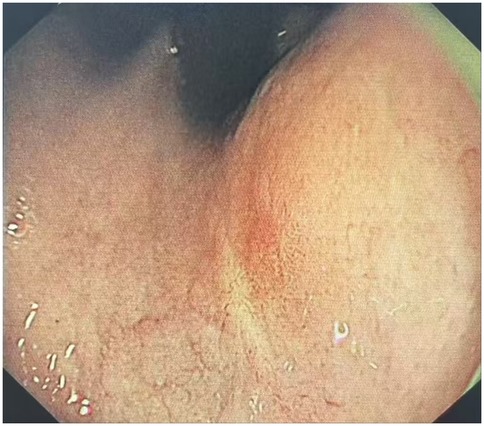

The clinical timeline was as follows: T = 0 (initial presentation); T = 2 days (ESD procedure); T = 7 days (discharge). A follow-up visit was conducted at T = 6 months, during which the patient underwent gastroscopy in the outpatient department (Table 1). The results indicated that the patient's cardia mucosa was smooth and without protrusions (see Figure 4). Given the documented, albeit rare, association between GHIP and the development of gastric adenocarcinoma (3), a long-term monitoring plan was established. The patient is scheduled for repeat annual endoscopic surveillance for a minimum of 5 years. Furthermore, due to the known correlation with chronic mucosal inflammation, the patient's status for H. pylori infection and atrophic gastritis will be monitored closely; if present, more frequent biannual endoscopy would be recommended (4).

Figure 4. Endoscopic performance at 6 months post-ESD. The results indicated that the patient's cardia mucosa was smooth and without protrusions.

Repeat endoscopy at 3–6 months post-ESD was need to assess resection site healing. Annual endoscopy for ≥5 years should be conducted, given reports of adenocarcinoma developing during follow-up (13). Those with H. pylori infection or atrophic gastritis require biannual endoscopy (4). For this case, a follow-up visit was conducted for the patient (T = 6-month: follow up), who underwent a gastroscopy in the outpatient department. The results indicated that the patient's cardia mucosa was smooth and without protrusions.